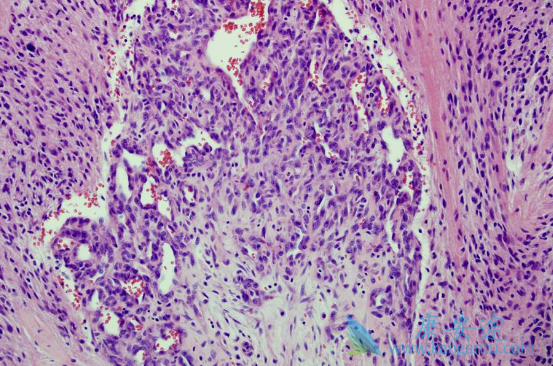

试验入选26例新诊断的GBM患者。所有患者术后分30次接受总剂量为60Gy的标准外束放疗。放疗同时给予替莫唑胺75mg/m2/d,40-42天,同时联合尼妥珠单抗(泰欣生)200mg/w,共6周。放疗完成后4周,给予6个周期的替莫唑胺辅助治疗(150-200mg/m2使用5天,28天一个周期)。首要终点为6个月的无进展生存率。采用免疫组化方法分析EGFR基因在肿瘤组织中的表达。

结果患者耐受性良好,且没有出现III级以上的毒性反应。中位无进展生存(mPFS)为10.0月,中位生存期(mOS)为15.9月。6个月的无进展生存率和总生存率分别为69.2%和88.5%。没有发现疗效与EGFR表达情况的关系。在治疗新发多形性胶质母细胞瘤的中国患者时,尼妥珠单抗(泰欣生)同步放疗、替莫唑胺及替莫唑胺的辅助治疗显示了良好的安全性和耐受性,生存时间与采用标准治疗的历史数据近似。